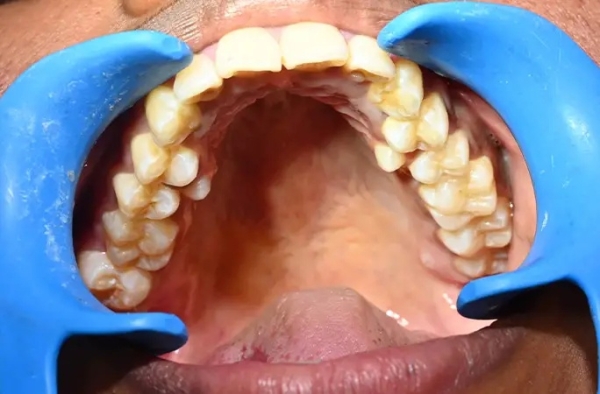

У девушки из Индии рекордное число зубов

У девушки на шесть зубов больше, чем у большинства людей: у жительницы Индии насчитали 38 зубов вместо 32-ух. При этом у неё нашли ещё два зуба, которые не прорезались. Больше только у мужчины из Канады — 41 штука.